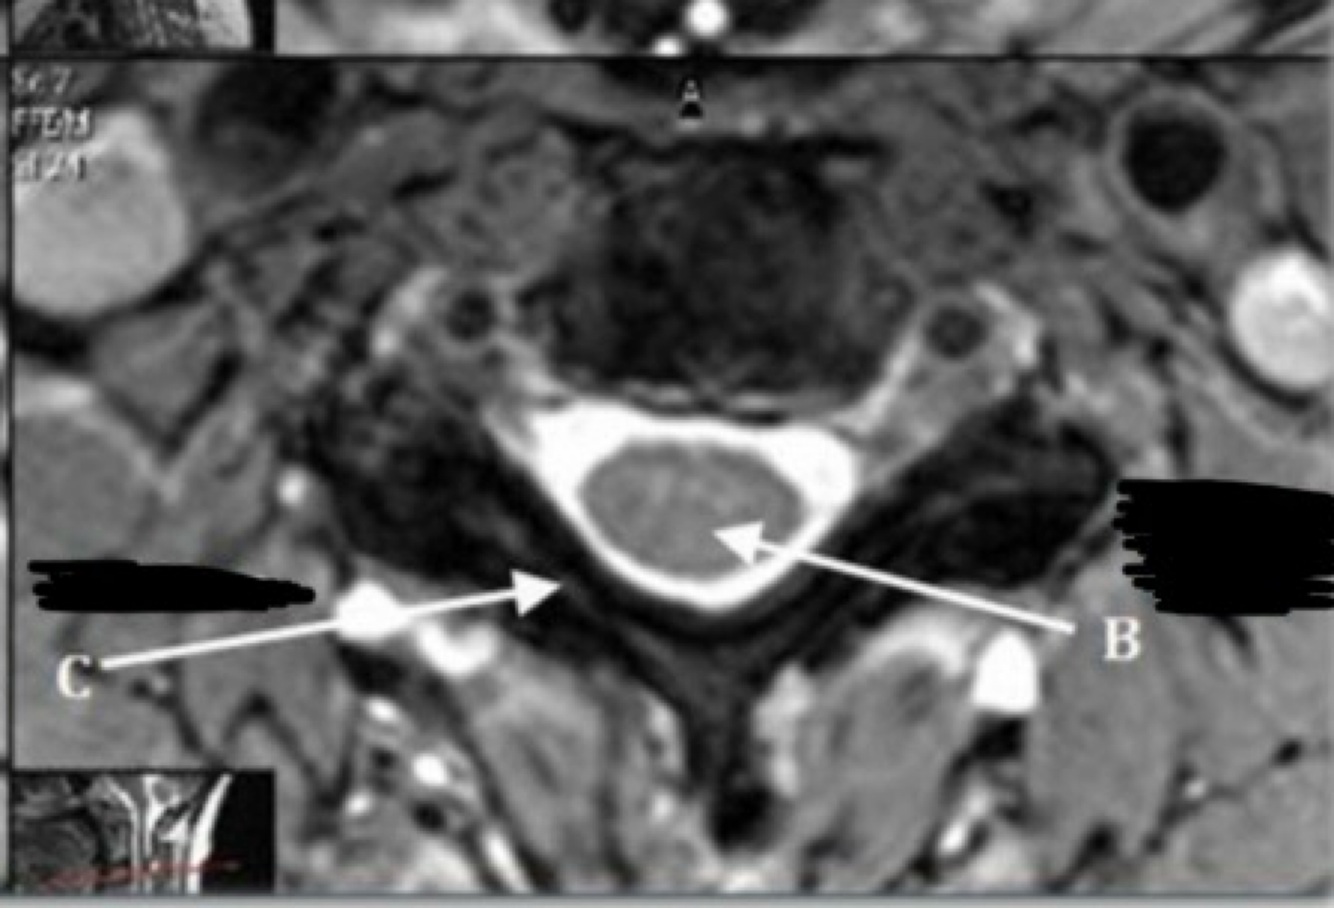

Q

What is letter A?

A

SPINAL CORD

20

What is letter B?

LIGAMENTUM FLAVUM

21

What is letter C?

SPINOUS PROCESS

22

What is letter D?

CSF

23

What is letter E?

VERTEBRAL BODY

24

What is letter F?

STERNUM